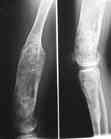

Диагноз: Дисхондроплазия. Варусная деформация дистального метафиза правой бедренной кости; состояние после оперативных вмешательств (1993 и1994 гг.).

Деформация правой нижней конечности с 6 месяцев (стала прогрессировать после года, с момента начала ходьбы). Поставлен диагноз болезнь Олье, варусная деформация, укорочение правой нижней конечности на 4,5 см. 1993 г. - операция остеоклазия на уровне очагов поражения в н/3 правой бедренной кости и в/3 правой большеберцовой кости с одномоментной коррекцией деформации и фиксацией костных фрагментов спицами Киршнера.После начала статической нагрузки (1994 г.) появился рецидив деформации и укорочения. Вторая операция - ЧКО АВФ, аппарат демонтирован через 2недели в связи с развившимся на уровне стержня переломом, после чего находилась в гипсовой повязке до консолидации костных фрагментов. Далеелечилась консервативно в гипсовой повязке. Выраженная деформация и укорочение правой нижней конечности. Относительная длина бедер: справа -34 см, слева - 51 см; анатомическая длина голеней: справа - 29 см, слева - 39 см. Величина варусной деформации на уровне дистального отдела правого бедра составляет - 80 град. Амплитуда движений в коленных суставах (разгибание/сгибание ): справа - 0/0/100 град.; слева - 0/0/30 град. Отмечается боковая и ротационная нестабильность на уровне правого коленного сустава. Амплитуда движений в голеностопных суставах - в норме. Тактика лечения? Заранее благодарю! С уважением,А.В.Владзимирский

Высылаю вам фото подобной больной, у нее тоже первая попытка до меня была безуспешной.

Нужен аппарат Илизарова стабильный с множеством спиц с напайкой, временной фиксацией колена аппаратом на голени. Наверное, проще первый раз начать с бедра, остеотомию выполнить прямо на уровне перехода очага в дистальный метафиз бедра. Дистракционный остеогенез вызовет перестройку хрящевой ткани в костную. Понадобится еще пара этапов.